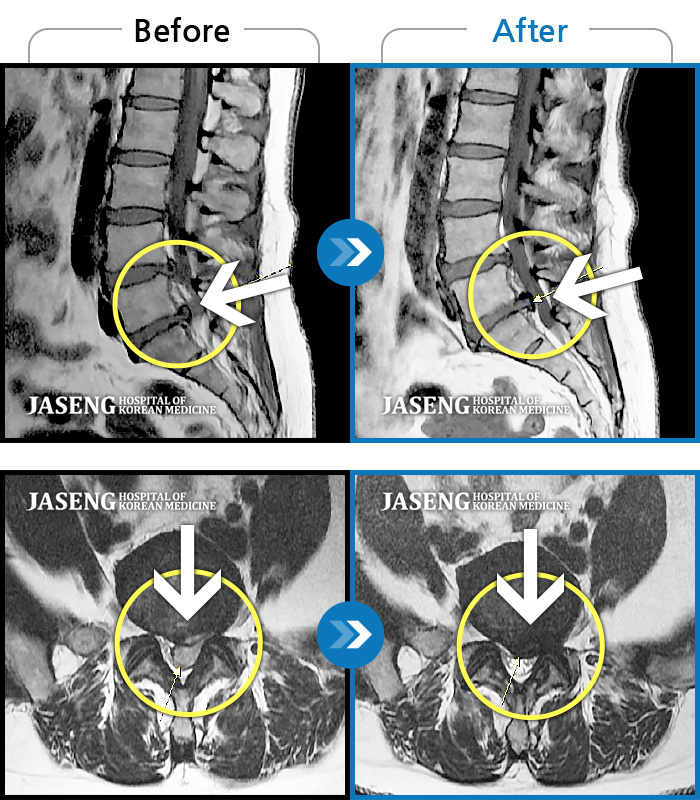

허리디스크

울산 · 정운석 원장

좌측 하지 외측이 저리면서 당김증상 및 감각둔화

촬영시기

2016.12.22 ~ 2022.11.24

2022.12.09